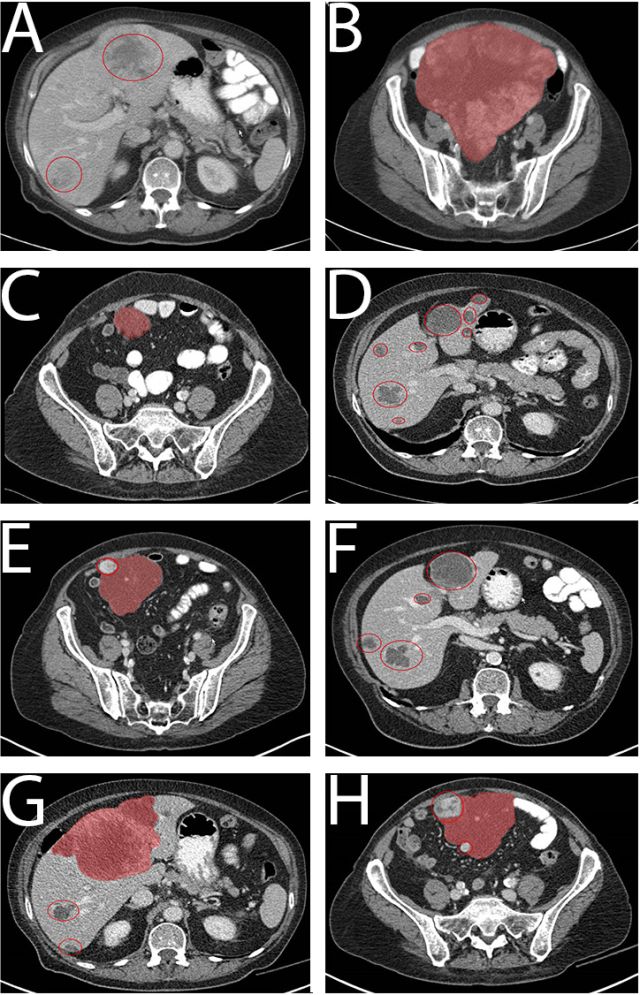

甲磺酸伊马替尼时代的复发性GIST治疗策略:一例非治愈性疾病

Platoff RM, Morano WF, Marconcini L, et al.

Department of surgery, Drexel University College of Medicine, Philadelphia, PA, USA

Case Reports in Oncological Medicine, Volume 2017

摘要:58岁男性,因腹部隐痛,便秘一年就诊。腹盆腔CT提示一分叶状,19x18x10 cm增强明显的肿块,于2013年1月接受了R0的肿瘤切除,包括部分小肠和部分膀胱切除。病理诊断:起源于近端空肠的高分级GIST,8/10HPF,伴坏死。免疫组化结果提示CD117(+),β-catenin(+),Vim(+),SMA(+)。C -Kit,PDGFRA基因未检测到突变,复发分险为90%,术后接受伊马替尼400 mg辅助治疗,伴有1级腹泻。在伊马替尼辅助治疗中的2016年5月CT随访发现左下腹近乙结肠处一3.5X2.8 cm的占位,给予伊马替尼800 mg口服,2016年7月复查CT提示PD,原肿瘤增大至4.0x3.3x3.2 cm,压迫乙结肠,新发2个病灶,分别为:脐周2.5x2.4x2.1 cm的病灶,右上腹5.3x3.7x2.1 cm的病灶。2016年7月手术,探查发现除原复发病灶,在右下腹另有一结节,行小肠切除+右上腹肿块切除+乙结肠切除+右下腹结节切除术。病理提示为高分级GIST,切缘(-),c-Kit未检测到基因突变。NGS提示可能对舒尼替尼敏感的野生型,术后给予舒尼替尼。2017年5月CT提示无肿瘤复发,每三个月建议随访一次。随后文章根据现有的文献讨论了原发性GIST的治疗和复发转移性GIST的综合治疗。